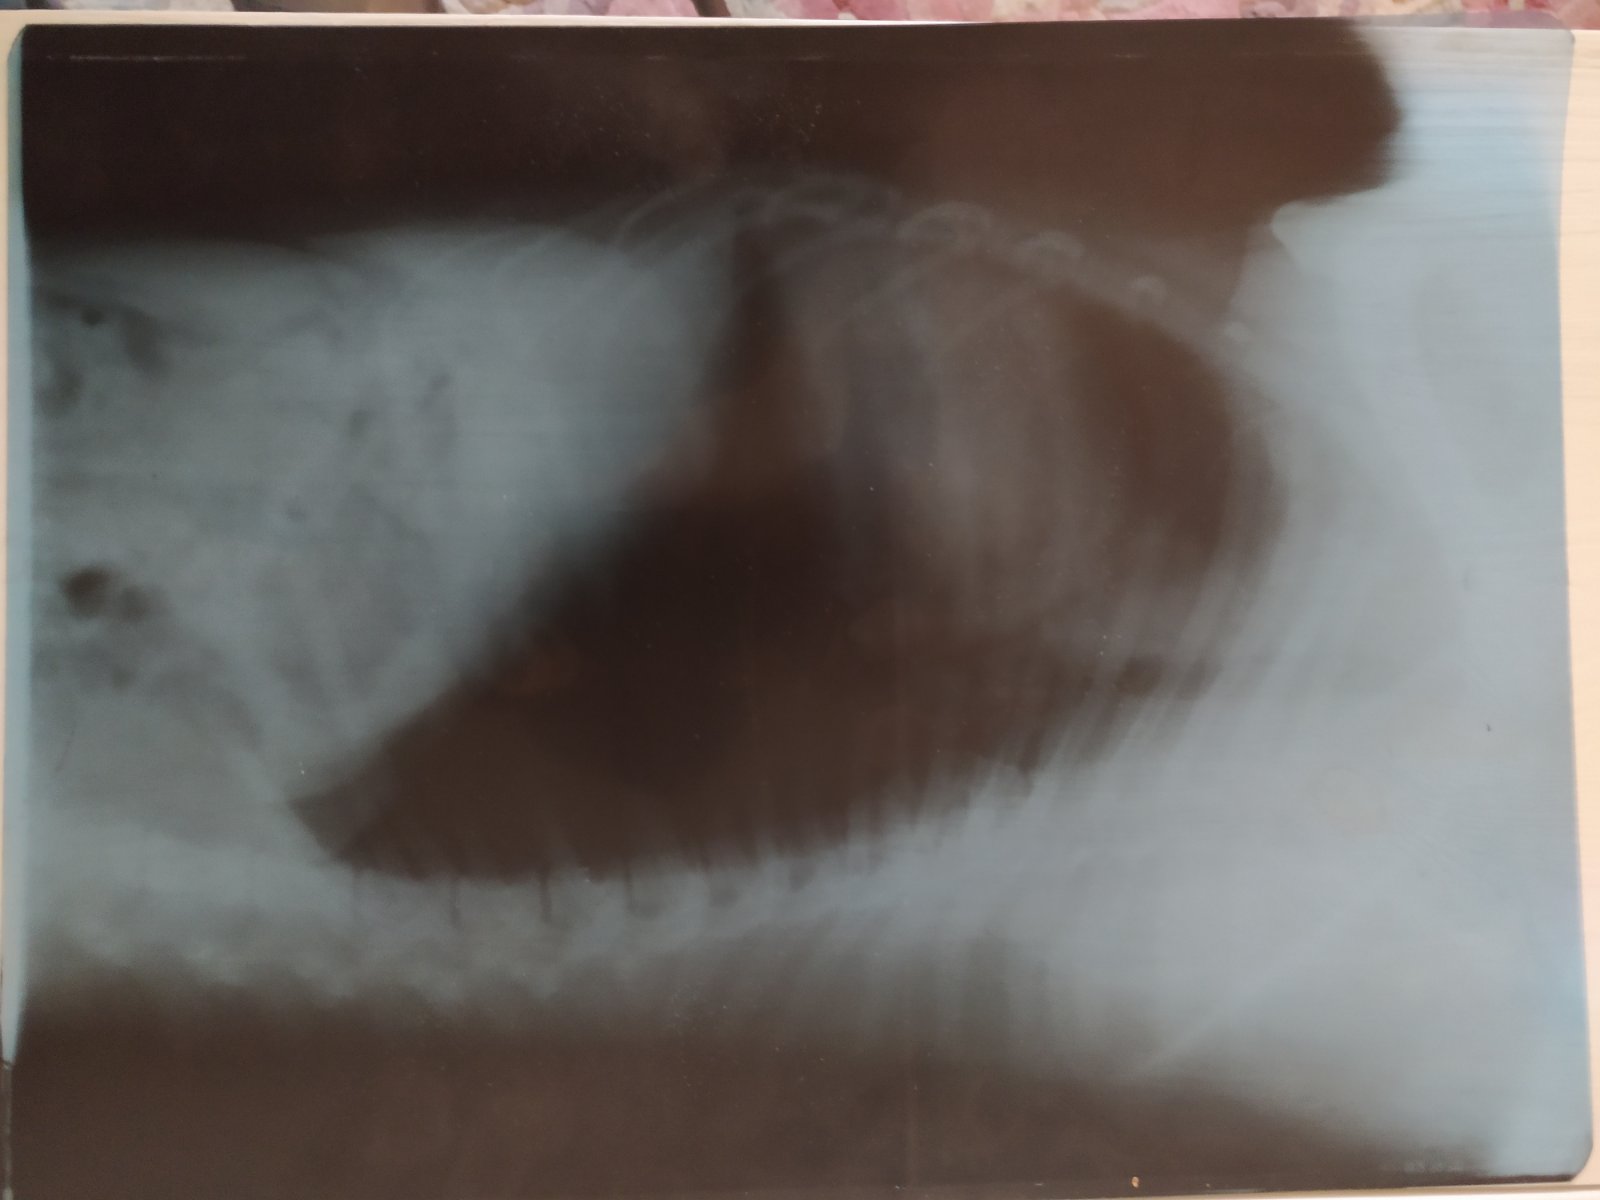

Макс сейчас в отличной физической форме, очень крепкий, мускулистый, крупный. Видимо, бродяжничал все же недолго. По здоровью: возможно, проблема с задней лапой (осторожничает при прыжках, разлизывает, не дает трогать). Небольшие проблемы с желудком, скорее всего из-за разнобойного питания на передержках. Еду перебирает. На натуралке какахи, простите, не те, а сушку не ест. Приучаю потихоньку. Уже разок стрескал с аппетитом корм, замоченный в бульоне. Надеюсь, так скоро привыкнет к сушке и желудок нормализуется. Ну и, конечно, нужно проглистогонить, прокапать от блох/клещей, сделать прививки и ветпаспорт. Завтра собираемся к ветеринару, о результатах отпишусь.